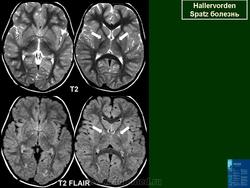

ГМ. Галлервордена - Шпатца болезнь. +

Галлервордена - Шпатца болезнь

Болезнь Галлервордена - Шпатца - наследственное заболевание экстрапирамидной системы, связанная с нарушением обмена железа и липидов и повреждением бледного шара и черной субстанции. Тип наследования аутосомно-рецессивный. При патоморфологическом исследовании характерным признаком является гиперпигментация бледного шара и черной субстанции. Обнаруживается пигментация коры полушарий большого мозга и таламуса. Пигмент находится внутри невронов и глиальных клеток, расположенных около сосудов; содержит железо (вместе с тем каких-либо нарушений обмена железа в организме не обнаружено). Наблюдаются утолщение и фрагментация аксонцилиндров в пораженных областях. Постепенно наступает дегенерация невронов коры полушарий большого мозга и мозжечка. Характеризуются нарастающей экстрапирамидной ригидностью, гиперкинезами (атетоз, торсионная дистония), затем развивается акинетико-ригидный синдром, пирамидная микросимптоматика, снижение интеллекта. Течение медленно прогрессирующее на протяжении 10 - 20 лет.

"Глаз тигра"-наглядно и красиво.